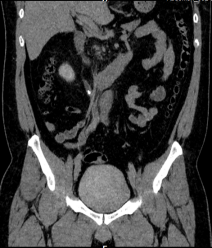

Chẩn đoán hình ảnh mô mềm tiên tiến cho vùng bụng.

Tăng cường độ tương phản I-ốt.

Hỗ trợ đánh giá an toàn cho bệnh nhân.

Đảm bảo hình ảnh chất lượng cao.